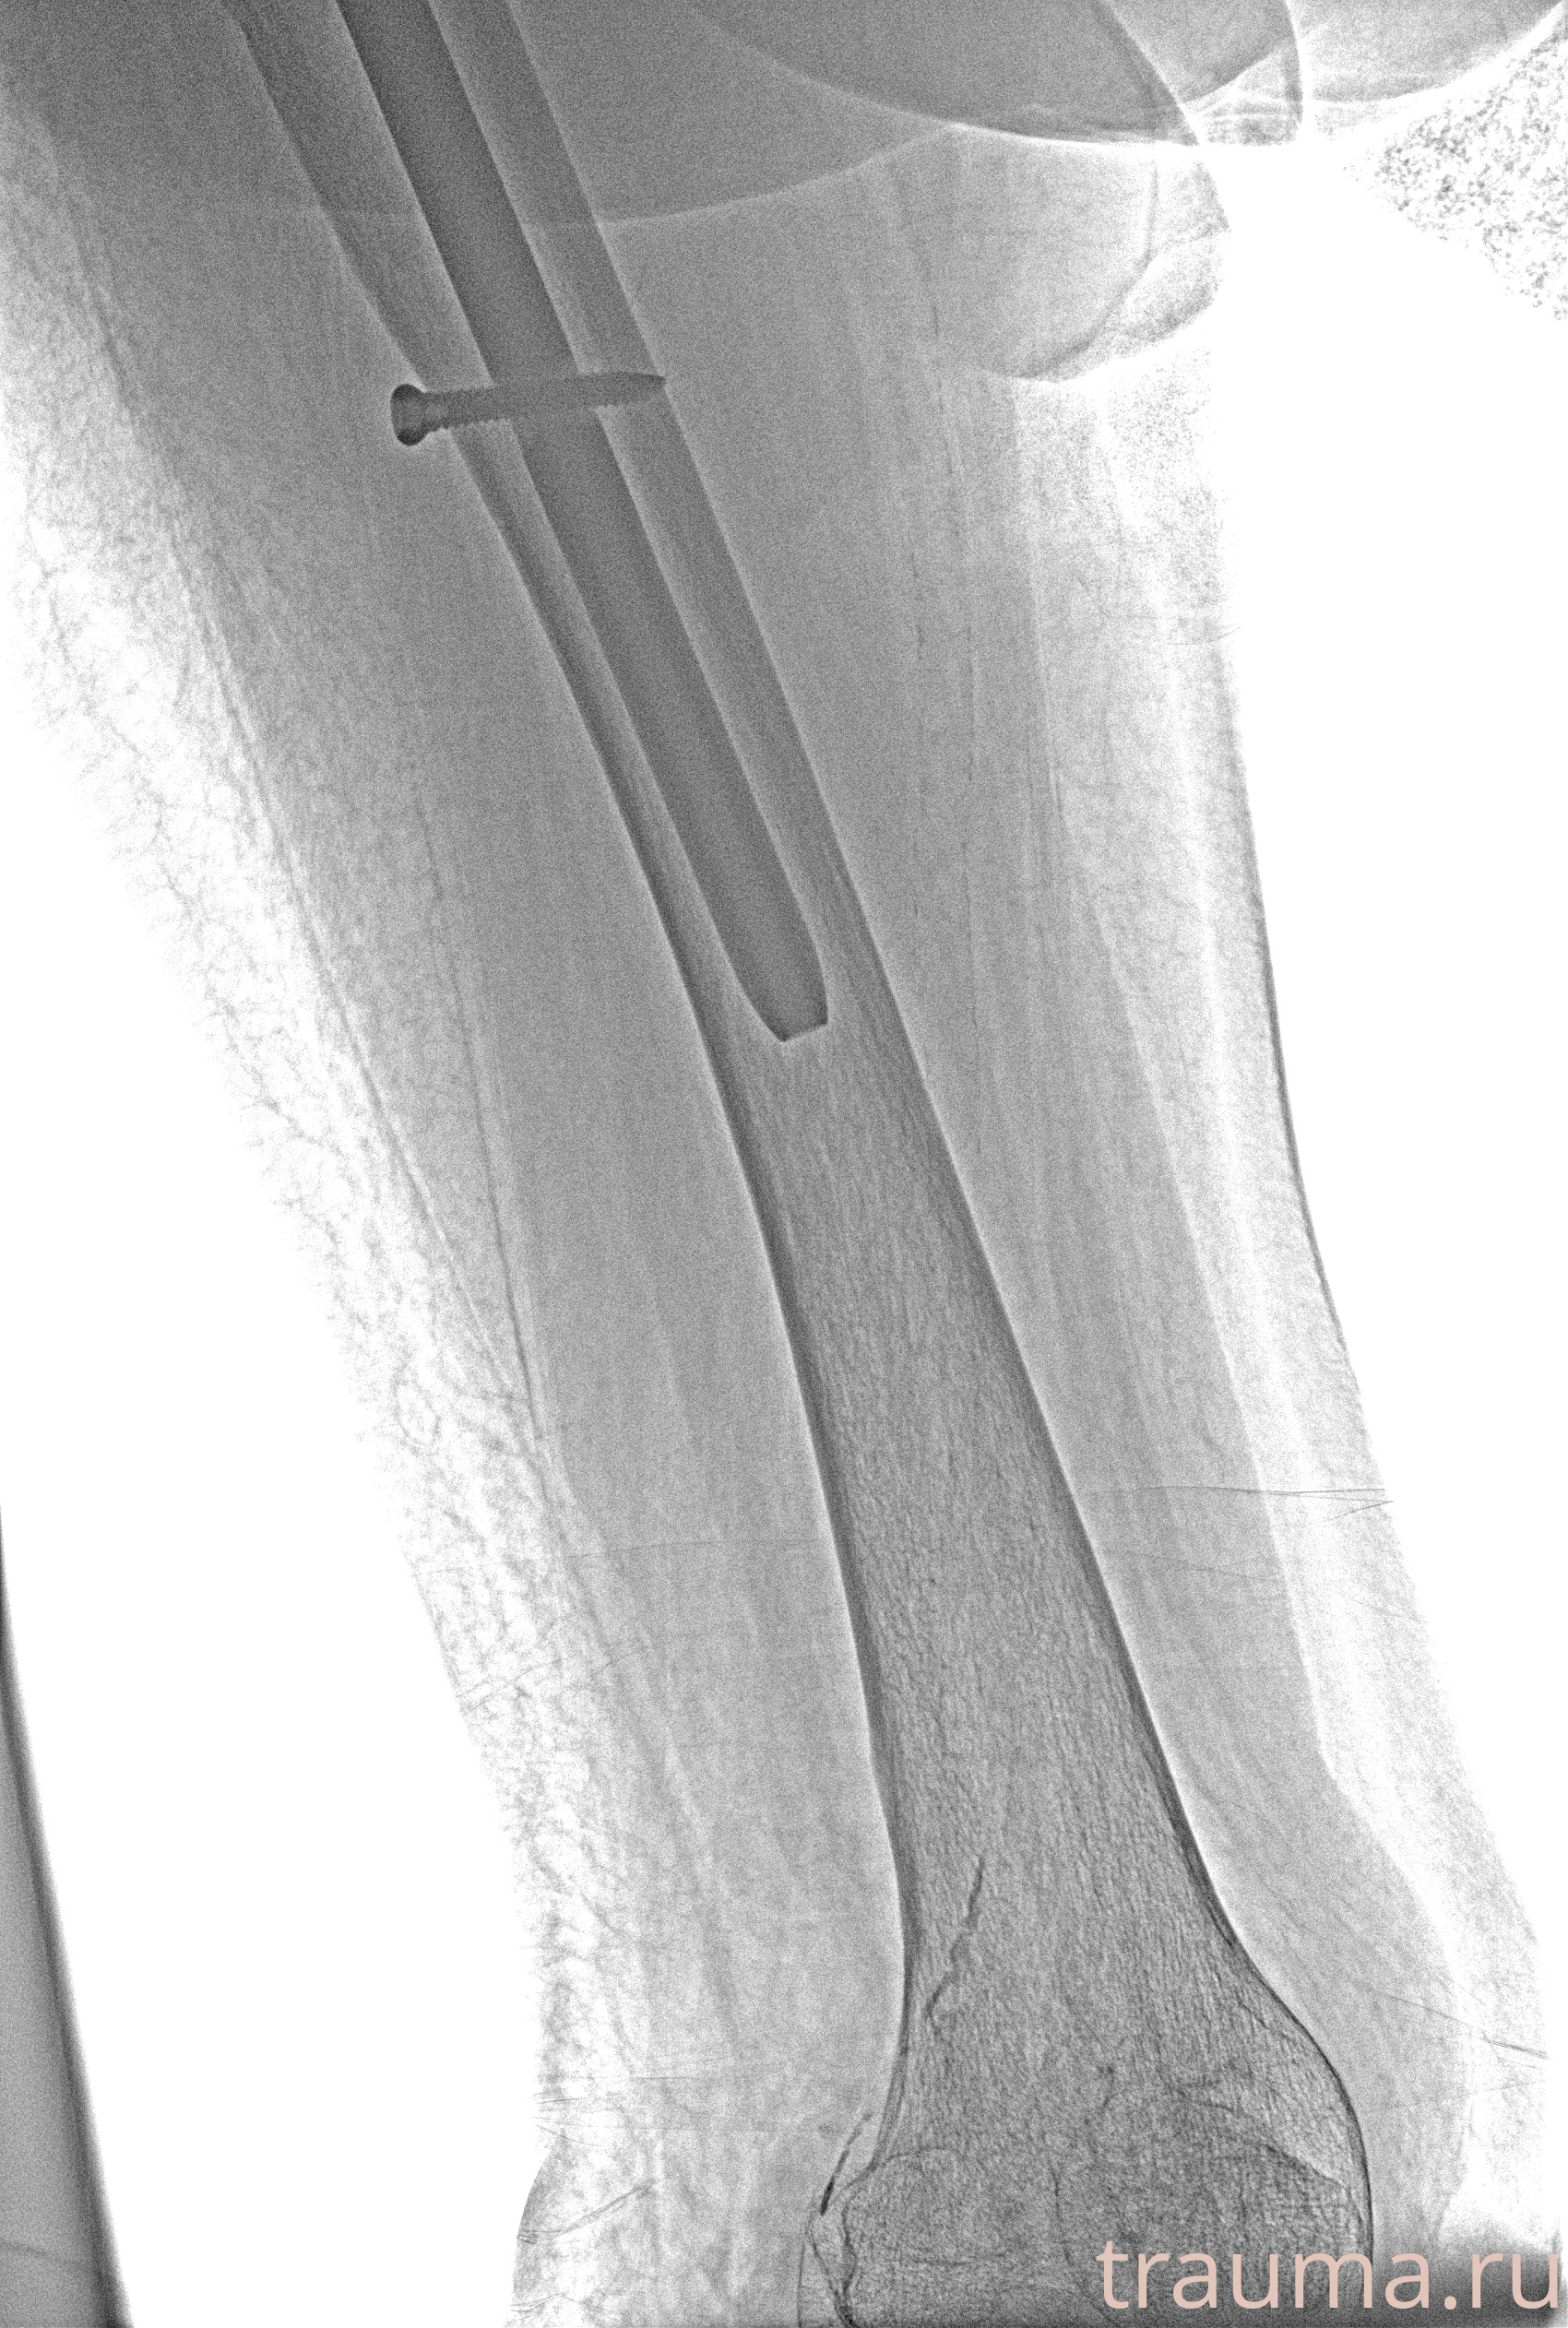

Рентгенограммы

Рентген на дому: по вашему адресу приезжает врач-рентгенолог, травматолог-ортопед с мобильным рентгеновским аппаратом, проводит диагностику травмы или заболевания, делает необходимые рентгенограммы, дает рекомендации по дальнейшему лечению. Получить качественные снимки в домашних условиях возможно благодаря уникальной методике, разработанной МосРентген Центром для института  Склифосовского